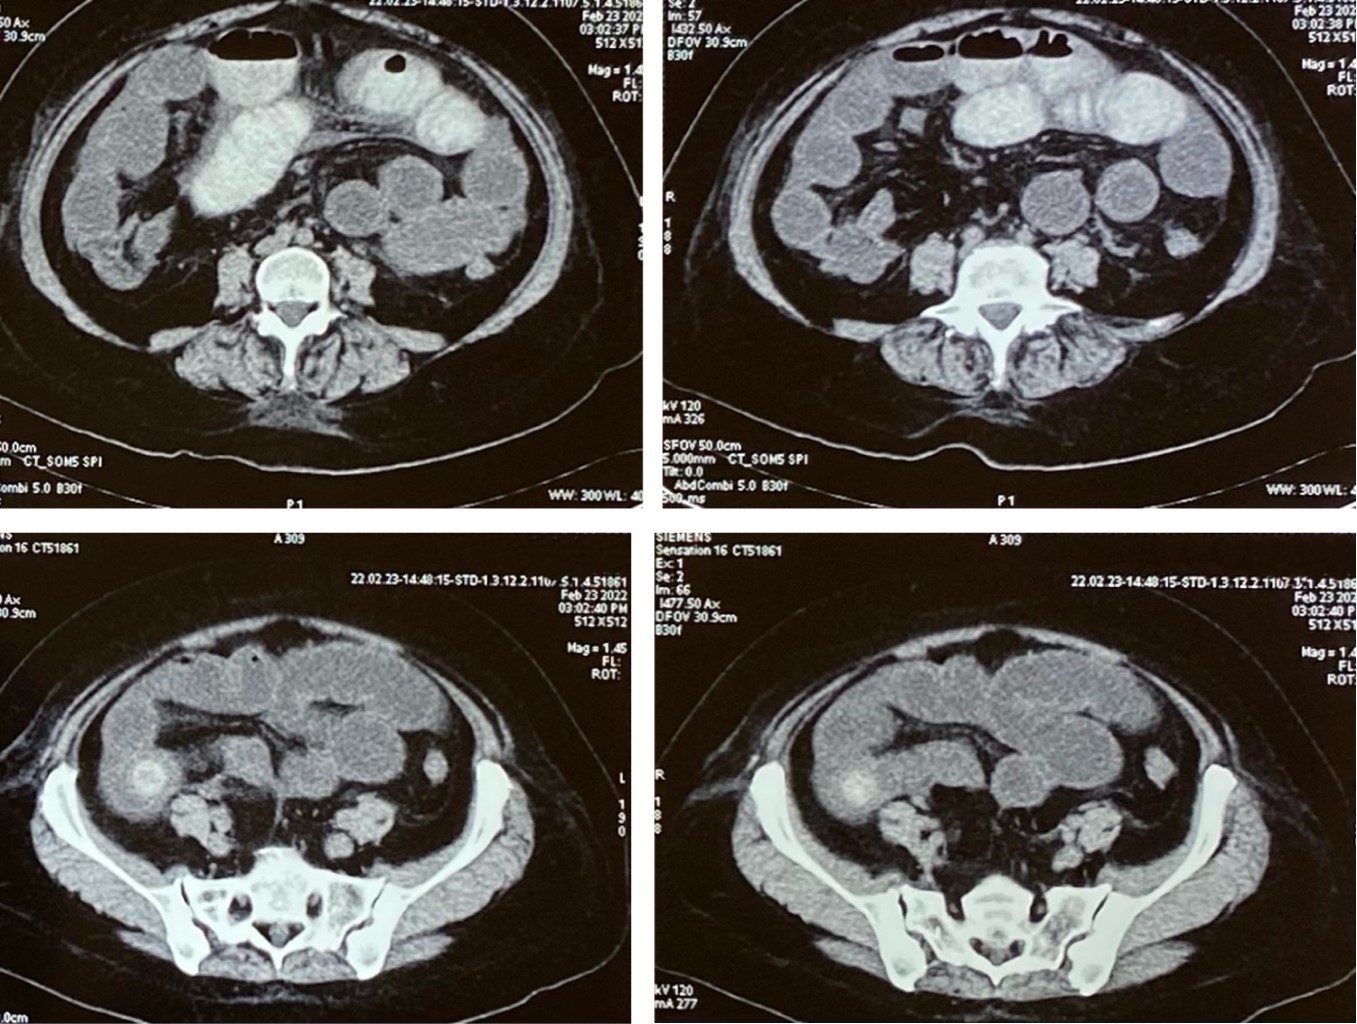

Paciente femenino de 58 que acude al servicio de urgencias por presentar cuadro clínico de ocho días de evolución caracterizado por dolor en epigastrio 9/10 puntos en la escala visual análoga, tipo punzante acompañado de náuseas que progresaron a vómitos de contenido gastrobiliar, evacuaciones y canalización de gases presentes. Se inició manejo con antiácidos por médico particular previo al ingreso a urgencias sin mostrar mejoría de sintomatología. A la exploración física muestra como hallazgos de relevancia distensión abdominal con dolor a la palpación superficial y profunda localizado en epigastrio y mesogastrio; timpanismo generalizado a la auscultación y peristalsis disminuida. No se encuentra resistencia muscular ni datos de irritación peritoneal al momento de su ingreso. Como antecedentes de importancia refirió alérgica a dextrometorfano y penicilina. Negó antecedentes de cuadros dolorosos abdominales sugestivos de colecistitis. También se negaron enfermedades crónico degenerativas y cirugías. En sus paraclínicos presenta leucocitos 18.13 × 103/mL, con neutrófilos 15.56 × 103/mL, linfocitos 1.44 × 103/mL, hemoglobina 11.60 g/dL, hematocrito 34.60%, plaquetas 359 × 103/mL, creatinina 0.60 mg/dL, nitrógeno ureico 8.6 mg/dL, urea 18.5 mg/dL, sodio 138 mEq/L, potasio 3.3 mEq/L y cloro 104 mEq/L. Se realizó tomografía abdominal con contraste vía oral con reporte de vesícula biliar con material de contraste proveniente del duodeno, que mostró comunicación anómala entre ambas estructuras en relación con el trayecto fistuloso a nivel de la segunda porción del duodeno, asas de intestino secundario a múltiples niveles hidroaéreos secundario a lito de 24 mm en íleon distal a 40 cm de la válvula ileocecal (Figura 1) con distensión de asas intestinales proximales a ese sitio. Se colocó sonda nasogástrica en su primer día de ingreso hospitalario con un gasto de 1,400 cm3 en las primeras 24 horas. En su segundo y tercer día de estancia intrahospitalaria la paciente no tuvo evacuaciones, ni canalización de gases; presencia de significativa distensión abdominal y timpanismo generalizado, aun sin datos de irritación peritoneal. Durante el cuarto día de estancia intrahospitalaria previo a su intervención quirúrgica se reportó evacuación con expulsión de heces y el cálculo biliar.

Figura 1